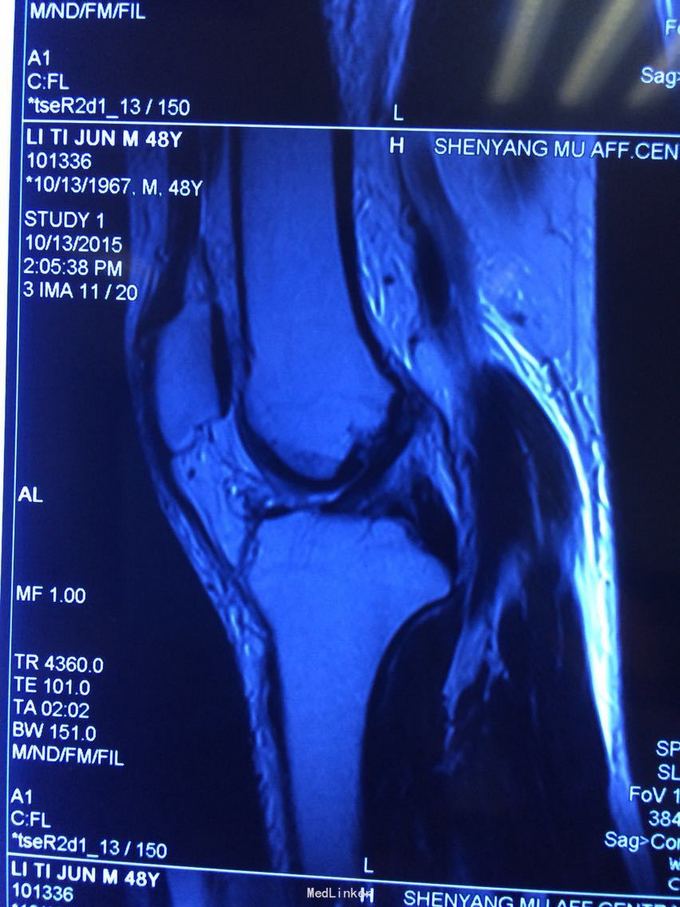

交通伤后膝关节疼痛,关节不稳。 患者交通伤,膝关节肿胀、疼痛,活动受限,肿胀消退后关节不稳。

查体:髌骨稳定,拉赫曼试验阴性,台阶征阳性3+,拨号征阴性,外翻0度阴性、30度阳性,内翻阴性。

诊断:膝关节多发韧带损伤,后交叉韧带、内侧副韧带 处理:给予关节镜下后交叉韧带重建,小切口修补内侧副韧带,取自体半腱股薄肌腱